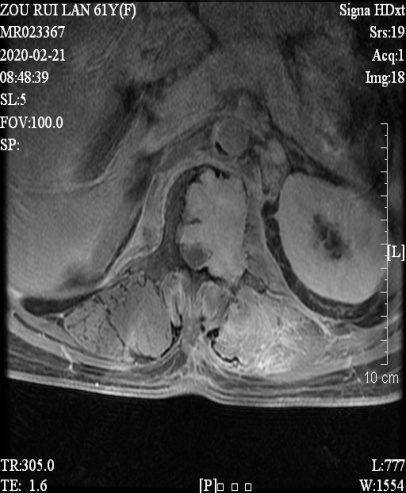

邹阿姨术前影像资料

邹阿姨入院后,骨伤科黄刚主任对其进行了仔细检查。腰椎CT显示腰1椎体及左侧有肿物,腹膜后及盆腔多发肿大淋巴结,腰椎骨质增生。

胸腰椎MRI发现胸10/11黄韧带肥厚、钙化,硬脊膜受压,椎管严重狭窄。PET-CT检查显示腰1椎体及左侧附件溶骨性破坏,伴代谢增高,考虑为骨原发恶性肿瘤。局麻腰椎穿刺活检考虑孤立性浆细胞瘤。